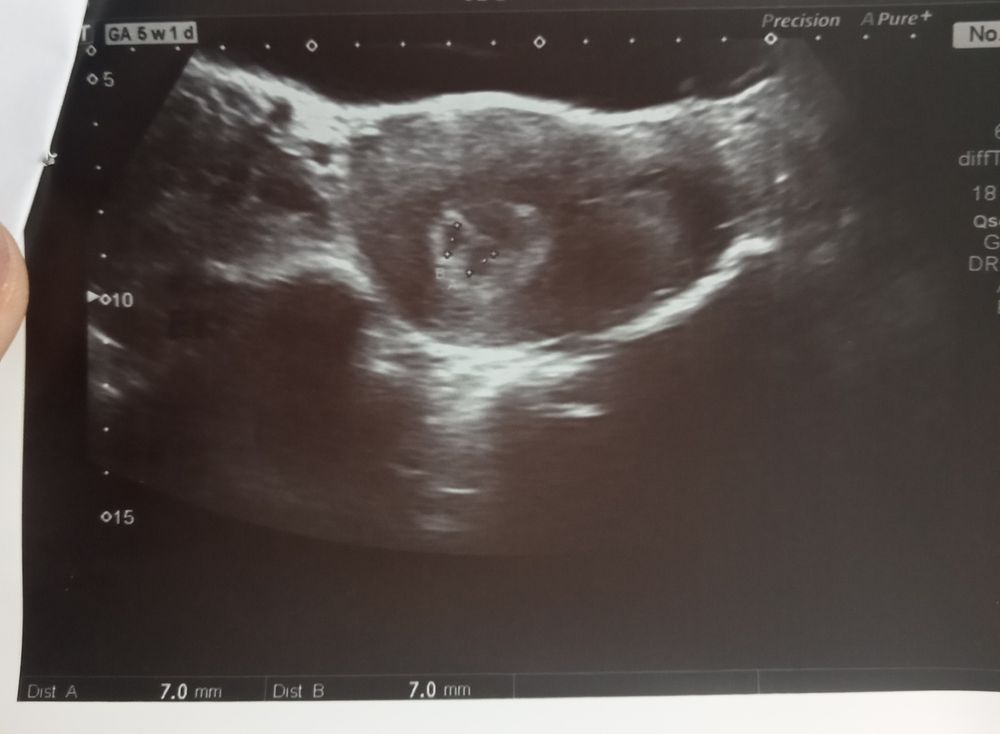

17 ДПП Узи ди-ди))

Попросила посмотреть на беременность, смотрел через жывот. И так...) У меня две крохи ди-ди.

Пока все в норме, след. УЗИ в 27 ДПП, надеюсь уже будет сб. Щасливы з мужем безумно но иногда охватывает паника))